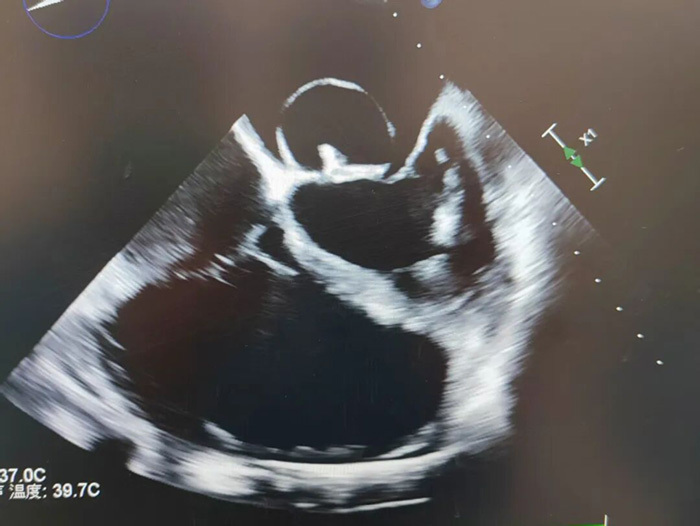

苏先生的心脏已濒临“报废”:二尖瓣被大量细菌赘生物侵蚀,前叶穿孔,前叶瓣体瘤,重度关闭不全,严重脱垂并返流;主动脉瓣被大量细菌赘生物侵蚀,二叶畸形,前瓣轻度脱垂,中度关闭不全;三尖瓣也受累反流;整个心脏因病变异常增大(“大心脏”),房问隔膨出,心包积液,心功能恶化至Ⅲ级,顽固性心衰合并肺部感染,保守治疗早已无力回天。“此时再不尽快手术清除赘生物、置换瓣膜,患者将彻底失去生机,而多重疾病加身无疑将手术风险值拉到最高。” 王院长坦言。

图片